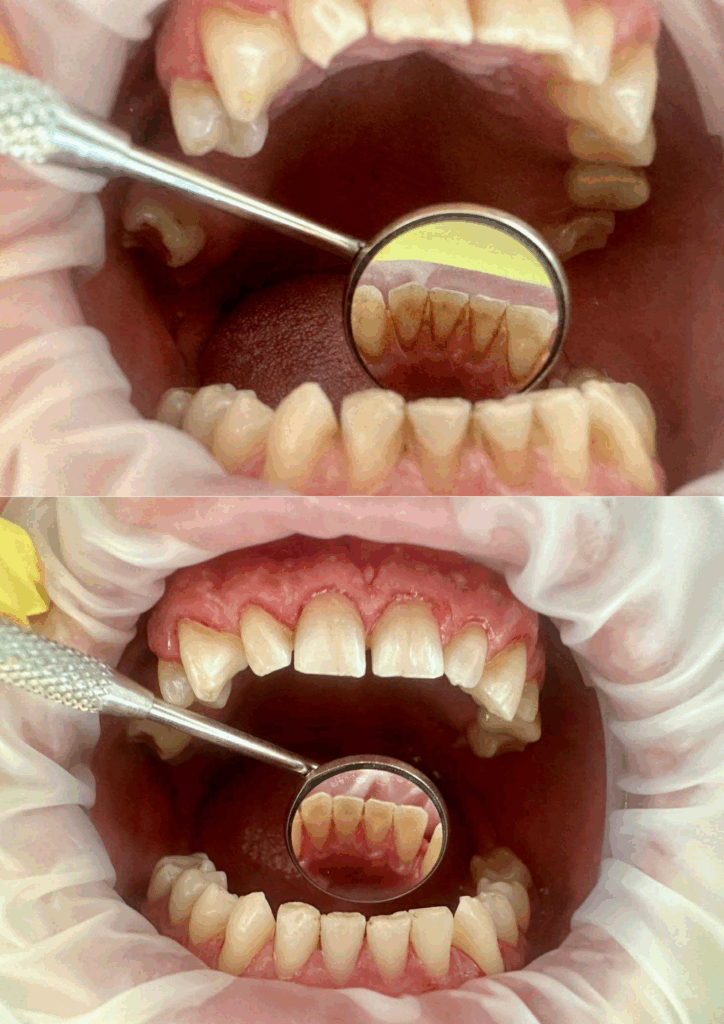

Wybielanie zębów metodą gabinetową – efekt przed i po

Zęby wybielone o dwa tony, wyrównanie koloru z koronami porcelanowymi